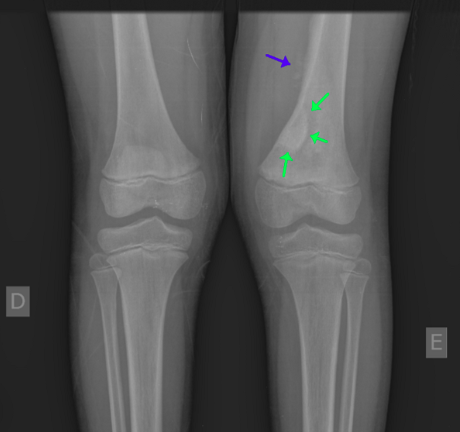

Geralmente, o tumor aparece nos ossos longos, como o fêmur, a tíbia, especialmente perto do joelho, e o úmero, próximo ao cotovelo. Cerca de 80% dos casos estão ligados ao fêmur.

Como o osteossarcoma afeta, na maioria dos casos, os ossos das pernas, o principal sintoma costuma ser dor na região afetada.